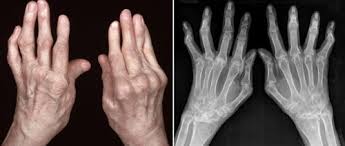

류마티스 관절염 진단 과정

류마티스 관절염의 진단은 여러 가지 방법으로 이루어집니다. 일반적으로 혈액 검사와 엑스레이, 염증 수치를 통해 진단을 받습니다. 혈액 내 류마티스 인자 및 항CCP 항체 검사로 류마티스 관절염을 확진할 수 있습니다. 진단 과정은 환자의 병력과 증상을 기반으로 하며, 전문의가 적절한 검사 방법을 선택하여 진행합니다. 이러한 진단 과정을 통해 류마티스 관절염인지 여부를 정확하게 판단할 수 있습니다.